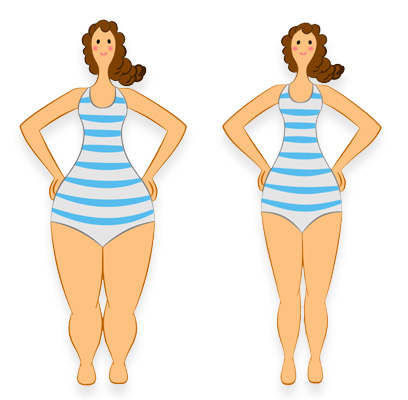

Bursa Haber Obez Degil Lipodem Hastasi Oldugunu Ogrendi

Lipodemi Obezite Ile Karistirmayin Bursada Bugun Bursa Bursa Haber Bursa Haberi Bursa Haberleri Bursa

Lipodemi Obezite Ile Karistirmayin

Lipodemi Obezite Ile Karistirmayin